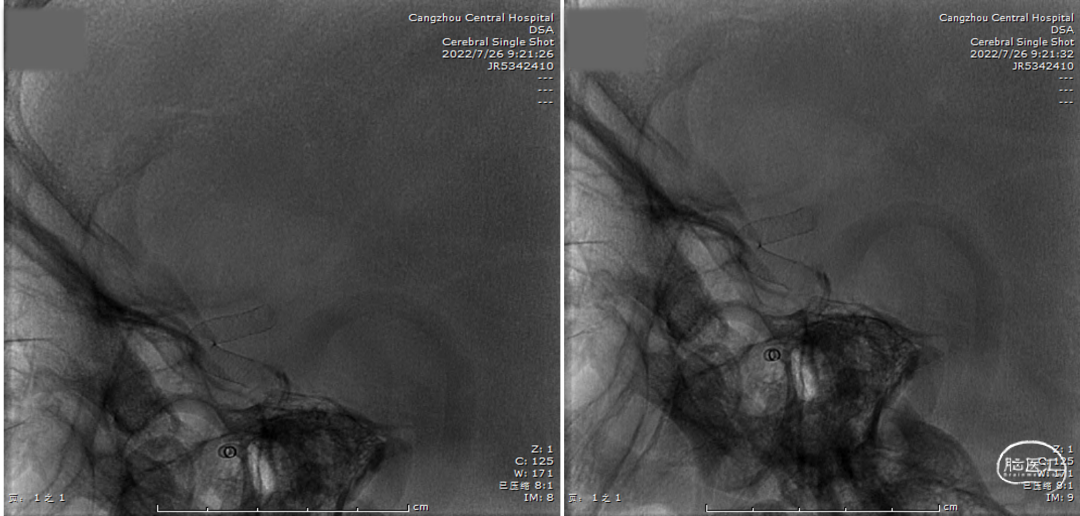

术中定位图像

Xper CT HiRes Cran.Stent